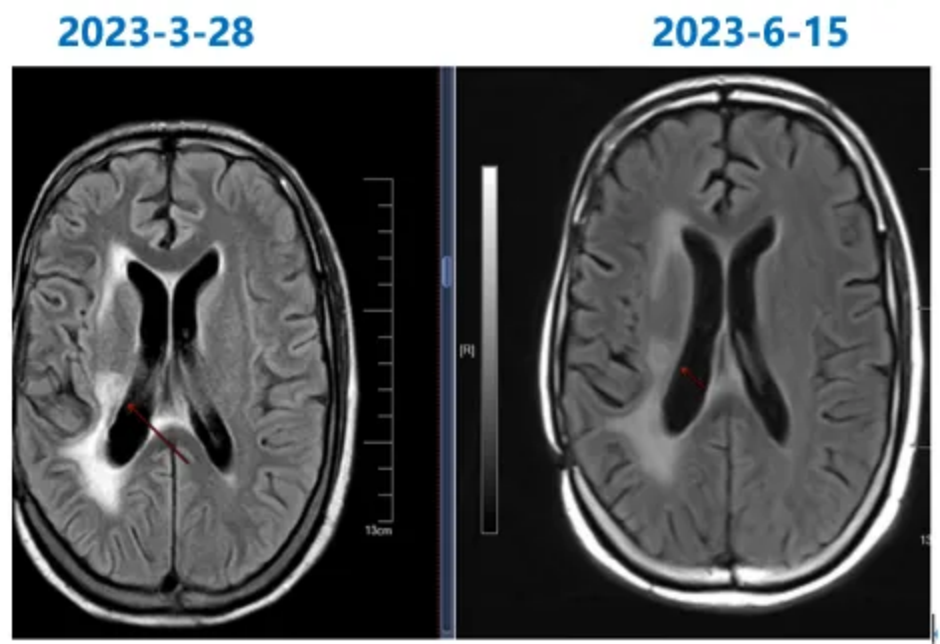

2023-3-28脑部MRI随访复查:右侧颞叶胶质瘤术后;右侧基底节区后部片状异常信号,较前(2023-1-28)范围基本相仿,建议定期复查;右侧侧脑室周围及胼胝体压部缺血灶;右侧基底节区陈旧性腔梗灶(图5)。

图5靶向+替尼泊苷治疗前后脑部MRI图像

2023-6-15随访复查颅脑MRI平扫+增强:右侧颞叶胶质瘤术后;右侧基底节区后部点状异常信号,较前(2023-3-28)缩小;右侧大脑脚华勒氏变性;右侧侧脑室周围及胼胝体压部缺血灶;右侧基底节区陈旧性腔梗灶;右侧基底节区亚急性腔梗灶?(图6)

图6 颅脑MRI图像